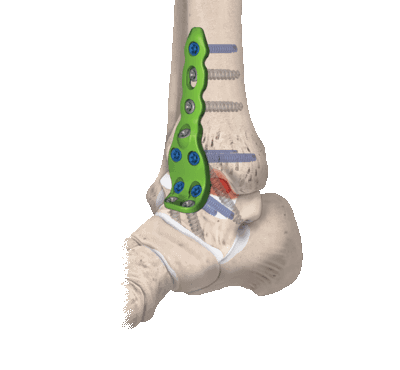

- Комбинированный. Эта техника подразумевает сочетание в одном хирургическом процессе двух способов: внутрисуставного и внесуставного. Так, хрящевые структуры с сустава полностью счищаются, внедряется аутотрансплантат, который фиксируют специальными металлическими пластинами.

3. Комбинированный. Сочетание в одном хирургическом процессе внутрисуставного и внесуставного способов. Хрящевые структуры с сустава полностью счищаются, внедряется аутотрансплантат, который фиксируется специальными металлическими пластинами.